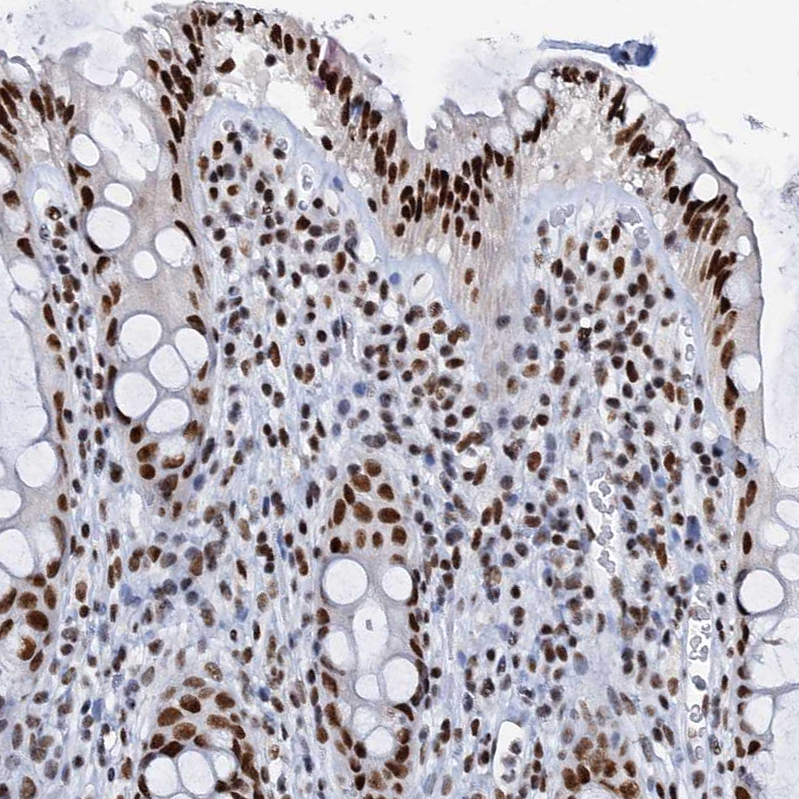

Immunohistochemical staining of human cerebral cortex, gastrointestinal, squamous epithelia and testis using Anti-SLTM antibody HPA040256 (A) shows similar protein distribution across tissues to independent antibody HPA040381 (B).